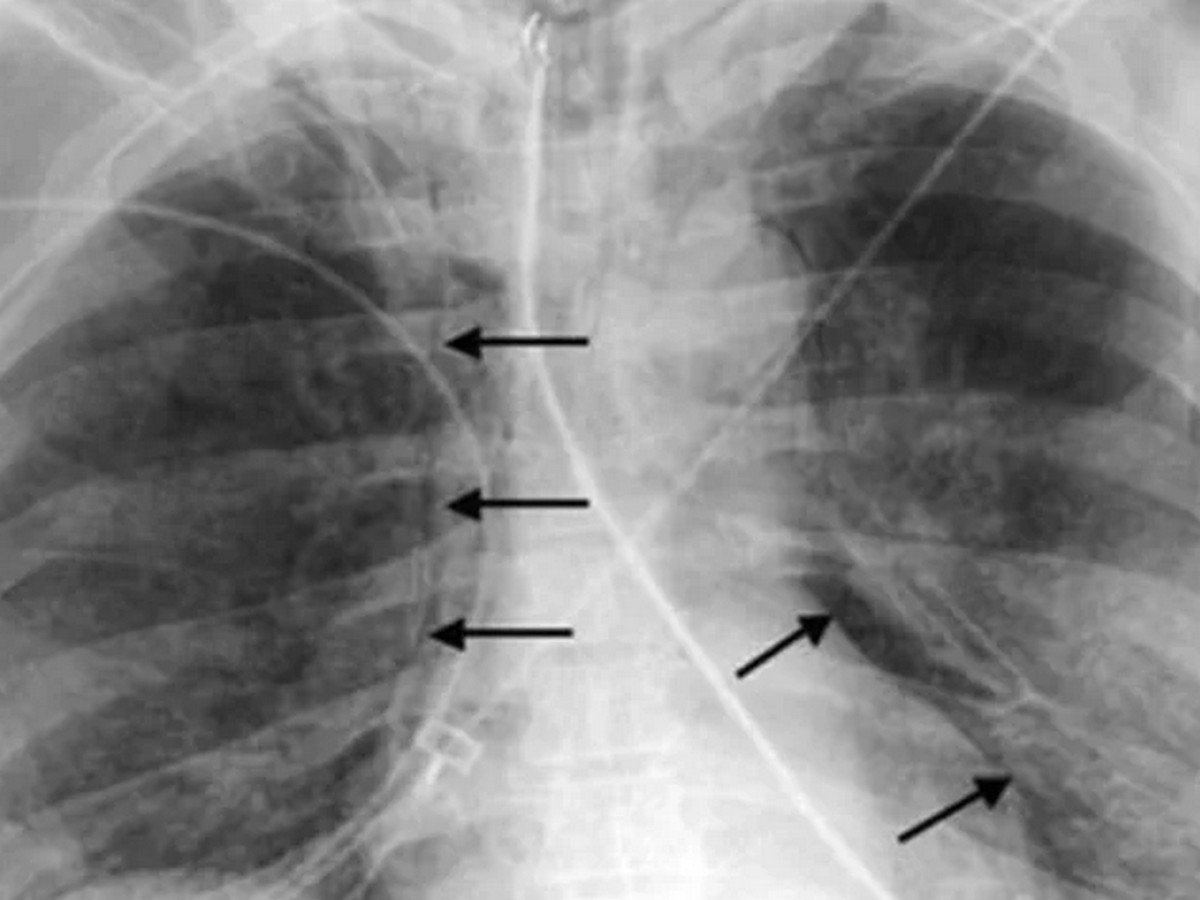

Регионалната здравна инспекция в Пловдив потвърди първи случай на ку‑треска за 2026 г. Засегнат е 67‑годишен мъж, който е приет в болница на 6 април с двойна бронхопневмония. След проведено лечение пациентът е изписан седмица по‑късно.

Ку‑треската е бактериална инфекция, причинена от Coxiella burnetii. Заразяването най-често става чрез вдишване на прахови частици, съдържащи бактерията, контакт с мляко, урина, изпражнения или секрети на заразени животни (обикновено овце, кози, говеда).

По-рядко заболяването се предава чрез кърлежи. Инкубационният период е между 9 и 40 дни. Хората са силно чувствителни към инфекцията и дори малък брой бактерии могат да доведат до заболяване.